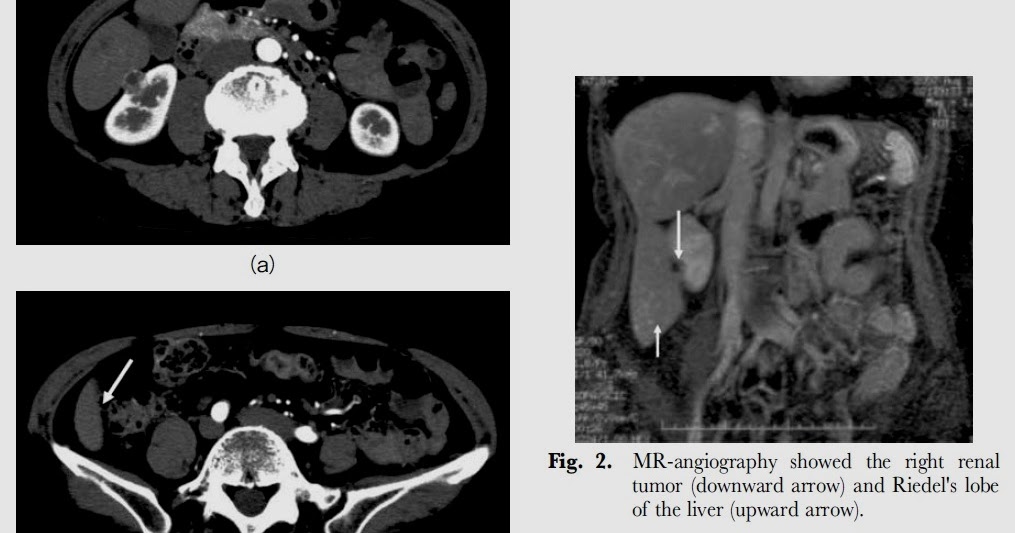

Cureus Coexistence of Riedel’s Lobe and Supernumerary Kidney as What Is Riedel Lobe the differential diagnoses include hepatomegaly and accessory liver lobes. riedel's lobe is a normal variant form of right liver lobe rarely found. Although most accessory lobes are. Here we report a case of 38 years old female with an incidental. riedel’s lobe is a rare anatomical variant of the liver with a downward projection of the anterior. What Is Riedel Lobe.

Riedel\'s Lobe Did you know these facts? Eurorad What Is Riedel Lobe riedel’s lobe is a rare anatomical variant of the liver with a downward projection of the anterior right. Although most accessory lobes are. the differential diagnoses include hepatomegaly and accessory liver lobes. Here we report a case of 38 years old female with an incidental. riedel's lobe is a normal variant form of right liver lobe rarely. What Is Riedel Lobe.

Riedel\'s Lobe Did you know these facts? Eurorad What Is Riedel Lobe the differential diagnoses include hepatomegaly and accessory liver lobes. Although most accessory lobes are. riedel’s lobe is a rare anatomical variant of the liver with a downward projection of the anterior right. Here we report a case of 38 years old female with an incidental. riedel's lobe is a normal variant form of right liver lobe rarely. What Is Riedel Lobe.

Riedel\'s Lobe Did you know these facts? Eurorad What Is Riedel Lobe riedel's lobe is a normal variant form of right liver lobe rarely found. the differential diagnoses include hepatomegaly and accessory liver lobes. Here we report a case of 38 years old female with an incidental. riedel’s lobe is a rare anatomical variant of the liver with a downward projection of the anterior right. Although most accessory lobes. What Is Riedel Lobe.